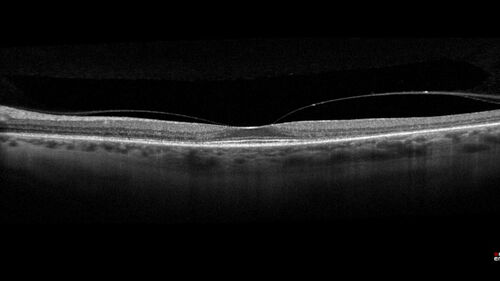

Hydroxychloroquine Toxicity

60 year old female received 6.5 mg/kg Plaquenil for 15 years and developed toxicity. VA 20/40 OD, 20/20 OS